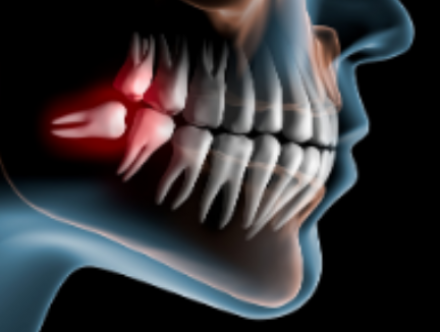

親知らずについて

親知らずの知識

親知らずは全て抜いたほうが良いのか?